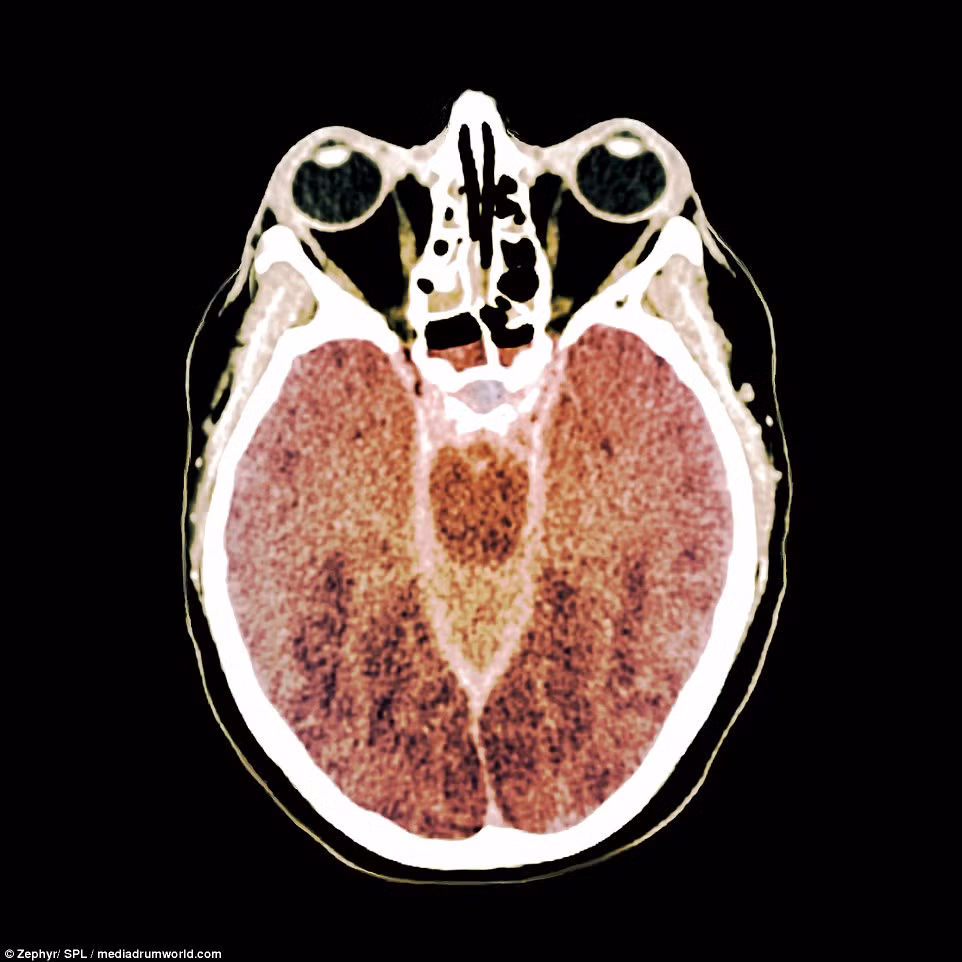

Đây là hình ảnh chụp CT của một bệnh nhân đang chỉ sống nhờ máy móc vì chết não, tức mất đi toàn bộ chức năng của cơ thể. Não chết do thiếu oxy, hay còn gọi là thiếu oxy huyết, mặc dù bệnh nhân đã được hồi sức sau tai nạn lặn. Ảnh cho thấy mật độ não bị giảm trên toàn bộ khối não, điều thường thấy ở những người bị thiếu oxy huyết.